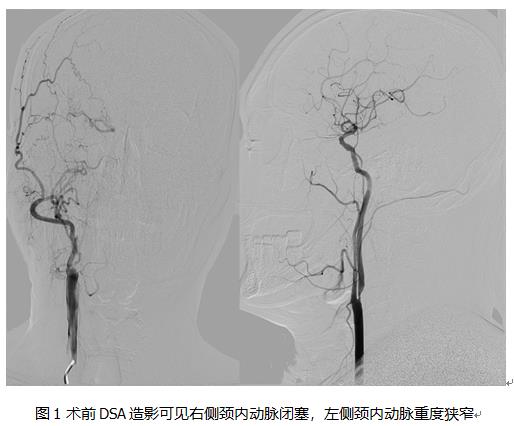

北京清华长庚医院12月12日电(通讯员 杨宇)近日,北京清华长庚医院血管外科收治1例右侧颈内动脉闭塞、左侧颈内动脉重度狭窄患者,成功实施左侧颈动脉内膜剥脱术(CEA)。CEA是剥除颈动脉斑块的经典术式,北京清华长庚医院的CEA手术安全性和疗效已达到国内领先水平。

血管外科医师认真分析了田老伯的病情和斑块性质,认为适宜开展CEA手术,充分准备后顺利完成手术,为患者解除了威胁。2019年发表的欧美最新研究已证实对侧颈动脉闭塞患者行颈动脉CEA术的安全性。